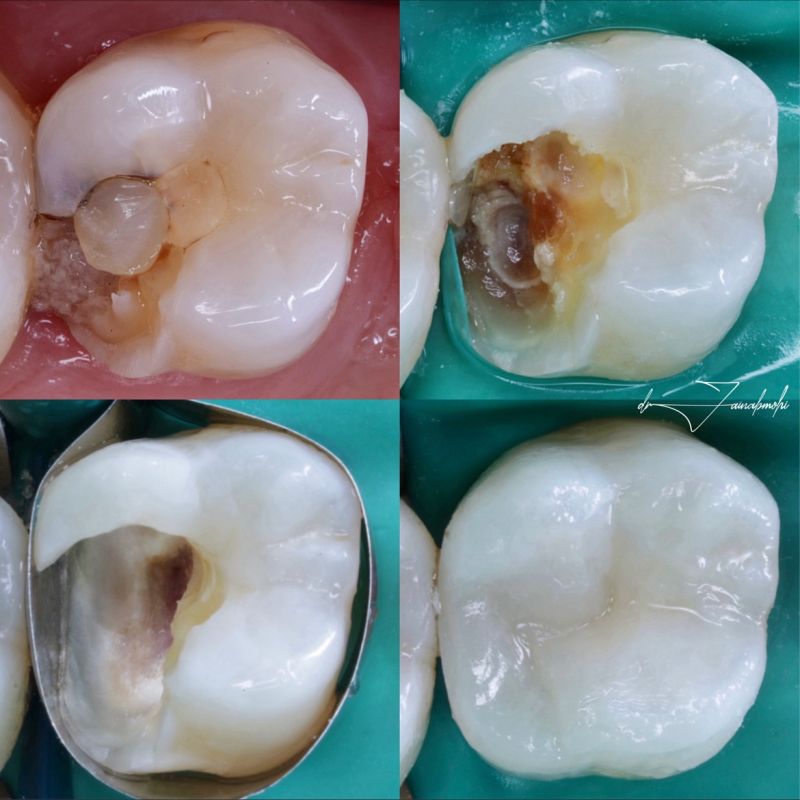

O capeamento pulpar direto é indicado quando há uma exposição direta da polpa dentária, seja de origem mecânica, traumática ou cariosa (desde que minimamente contaminada).

O objetivo é proteger diretamente o tecido pulpar exposto com materiais que promovam a cicatrização e a formação de dentina reparadora.

Entre os materiais utilizados, destacam-se o hidróxido de cálcio, o MTA (Mineral Trioxide Aggregate) e a biodentina.

Estes materiais são reconhecidos pela sua biocompatibilidade, capacidade de indução de formação de dentina e selamento efetivo.

O capeamento indireto, por sua vez, é realizado quando há uma cárie profunda, mas sem exposição da polpa.

A ideia é remover seletivamente a dentina infectada e preservar a dentina afetada, minimizando o risco de exposição e estimulando a remineralização ou a formação de dentina terciária.

O capeamento direto exige protocolo rigoroso de controle de contaminação e seleção precisa do caso.

Após o isolamento absoluto do campo operatório, realiza-se a remoção cuidadosa da lesão cariosa ou do tecido fraturado até a exposição pulpar.

Em seguida, realiza-se a hemostasia com solução salina ou hipoclorito de sódio diluído.

O material de capeamento é então inserido sobre o ponto de exposição.

Após isso, deve-se aguardar o tempo de presa do material e proceder com o selamento restaurador definitivo.

A seleção do material é fundamental: o MTA e a biodentina têm mostrado resultados superiores ao hidróxido de cálcio, devido à sua estabilidade, melhor selamento marginal e indução celular mais eficaz.

Após o isolamento absoluto, remove-se a dentina cariada superficial com brocas ou instrumentos manuais, deixando-se uma camada de dentina mais próxima da polpa que, embora afetada, pode ser remineralizada.

Aplica-se então um material com propriedades antibacterianas e bioativas, como hidróxido de cálcio ou cimento de ionômero de vidro modificado por resina.